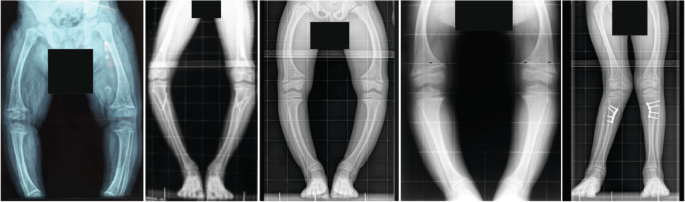

X-linked hypophosphataemia (XLH) is a rare metabolic bone disorder caused by pathogenic variants in the PHEX (phosphate-regulating endopeptidase homologue X-linked) gene, which is mainly expressed in bone (osteoblasts and osteocytes) and teeth (odontoblasts and cementoblasts). The incidence of XLH is 3.9 per 100,000 live births and the prevalence ranges from 1.7 to 4.8 per 100,000 people1,2,3. The pathogenesis of XLH is complex and incompletely understood. Many features of the disease can be explained by increased secretion of the phosphaturic hormone fibroblast growth factor 23 (FGF23) from bone. Binding of FGF23 to the FGF receptor 1–alpha-Klotho co-receptor complex results in downregulation of the sodium-dependent phosphate transporters NPT2a (encoded by SLC34A1) and NPT2c (encoded by SLC34A3), a decrease in 1,25-dihydroxyvitamin D (1,25(OH)2D) synthesis and an increase in 1,25(OH)2D degradation in the proximal renal tubules, ultimately causing hypophosphataemia and hypovitaminosis D4. The clinical consequences of XLH can include rickets, osteomalacia, bone pain, leg deformities (Fig. 1), premature fusion of the cranial sutures and disproportionate short stature that usually develops during the first 2 years of life5. Patients also show hypomineralization of teeth and are prone to tooth abscesses and periodontitis6 (Fig. 2). Adult patients with XLH may show pseudofractures due to osteomalacia as well as osteoarthritis, enthesopathies, spinal stenosis, hearing loss, depression and reduced quality of life7. The pathogenesis of osteoarthritis and enthesopathies and to what extent these are sequelae of certain primary manifestations of XLH is poorly understood8,9.

The patients show disproportionate short stature with genu varum (bowed legs) or genu valgum (knock-knees). The radiographs reveal severe leg bowing, partial fraying and irregularity of the distal femoral and proximal tibial growth plates. Note the lack of bone resorption features. Reprinted from ref. 17, CC BY 4.0.

Leg deformities that result from impaired bone mineralization are a hallmark of XLH in children (Fig. 1). These deformities often persist or even progress during treatment with phosphate supplements and active vitamin D, necessitating corrective orthopaedic surgery in about one-third of patients48,138,139. The availability of burosumab has fundamentally changed the approach to preventing and managing leg deformities in patients with XLH.